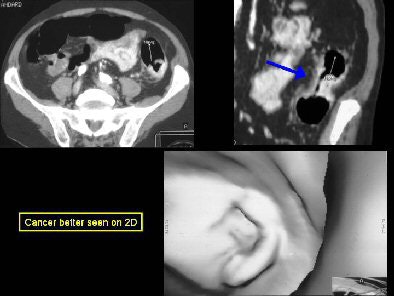

"Annular carcinomas are better evaluated on 2D views, and may be mistaken for an area of collapse on 3D," Yee wrote in her abstract.